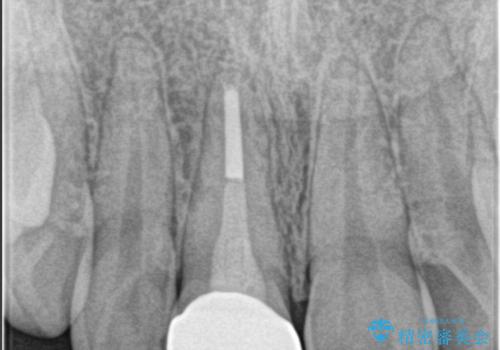

- 前歯が欠けたとの事で来院。

セラミックを希望されたので根管治療からやり直しました。

- ジルコニアクラウンスタンダード・仮歯 13.2万円 精密根管治療(リトリート)・ファイバーコア 12.1万円費用は治療当時の料金となります